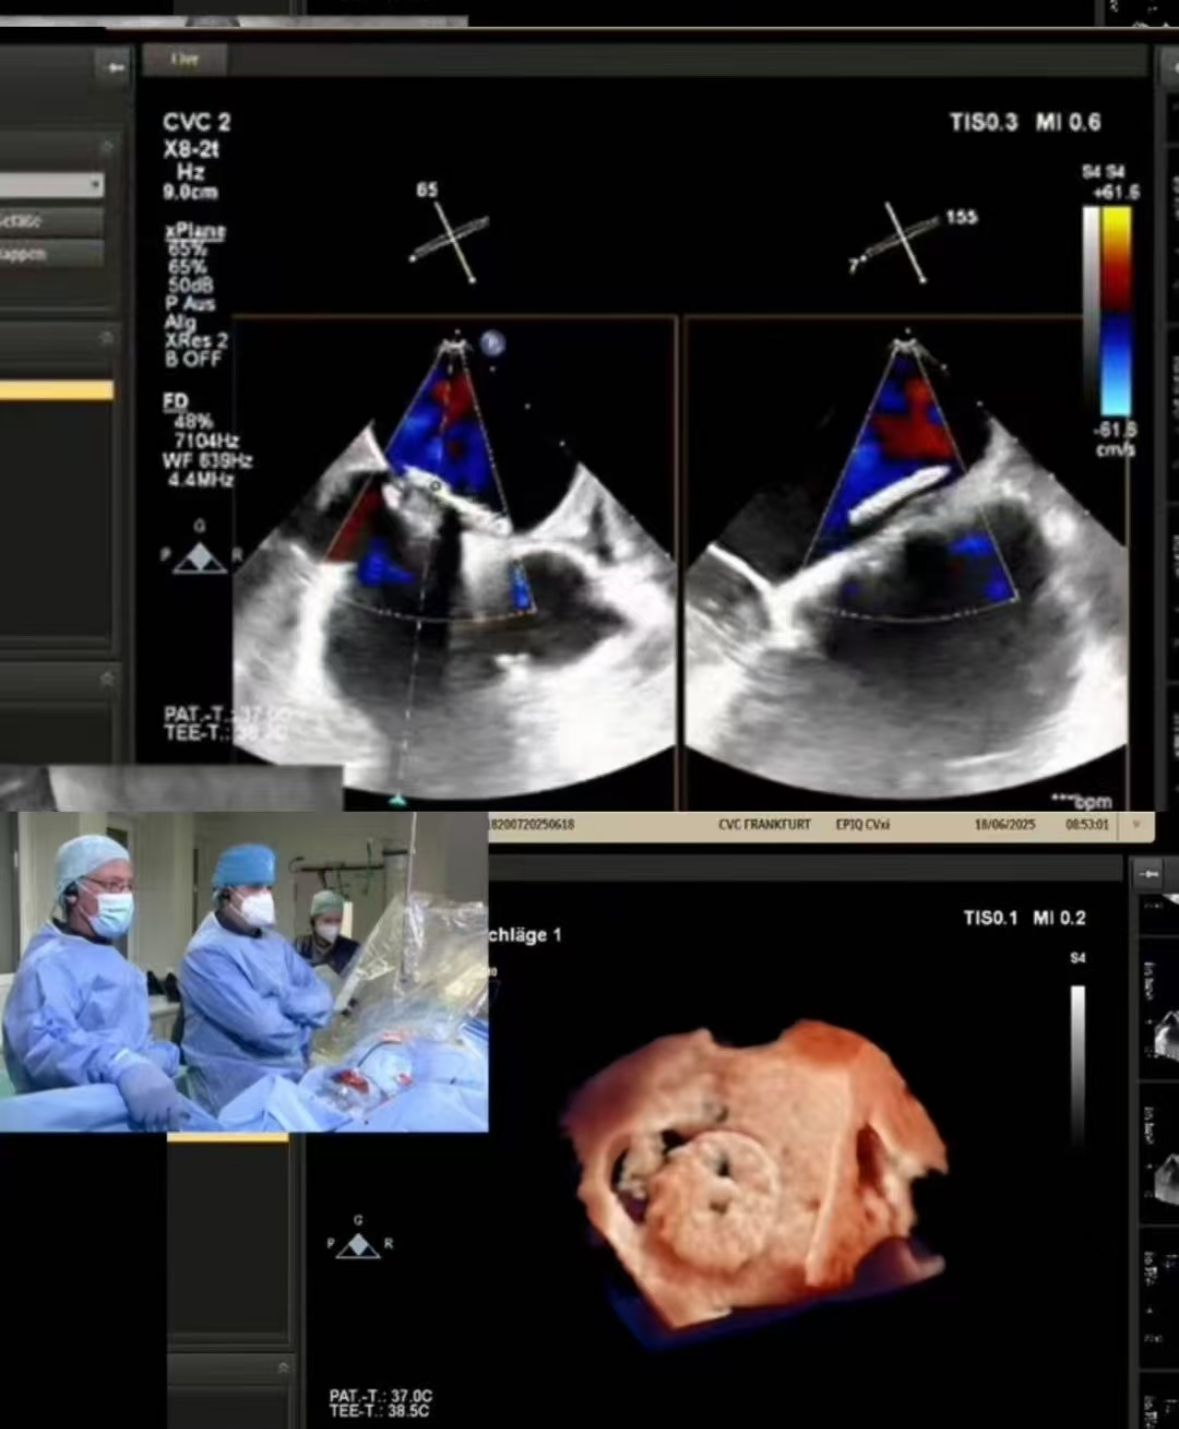

Thrilled to showcase our MemoSorb PFO Occluder – the world's first absorbable device (degrades to water & CO₂ within 1 year) – during a live broadcast from the Blue Room at CSI Frankfurt!

Streamed un cierre de FOP complejo realizado en CVC Frankfurt en una paciente de 60 años de edad con:

1. accidentes cerebrovasculares embólicos recurrentes (2014, 2021)

2. alergia severa del níquel (contraindicación para los dispositivos del metal)

3. derivación residual después del cierre anterior

2. cierre preciso: Implementación perfecta guiada por imágenes en tiempo real en anatomía desafiante (fenestración del túnel PFO).